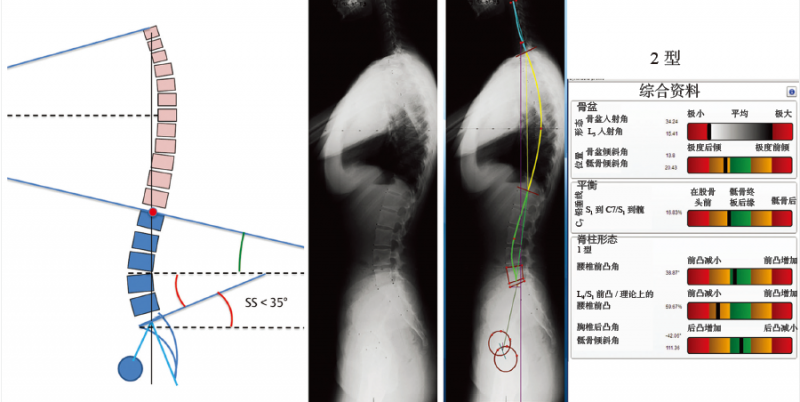

图 6-11 2型脊柱前凸

骶骨倾斜角<35°,临界点越来越高,越来越前,形成一个较长但平坦的下脊柱前凸(超过3个节段水平),接近一条直线,前后凸均较小。背部平坦协调